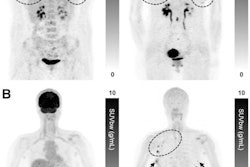

T1-weighted postgadolinium MR images (A and C) and F-18 FET-PET/MR images (B and D) centered at pituitary before (A and B) and after (C and D) transsphenoidal surgery. This patient with Cushing disease showed clear focal uptake (B) but no clear lesion on previously obtained and accompanying MRI (A). Postoperative tissue analysis did confirm resection of small pituitary adenoma/PitNET, and postoperative F-18 FET-PET showed no residual uptake (D). Image courtesy of the Journal of Nuclear Medicine.

The researchers analyzed results from 22 patients (68% women; mean age 48 years) who underwent F-18 FET PET/MRI at Erasmus MC between February 2021 and December 2022. All patients showed a clear pituitary tumor F-18 FET-PET/MRI, whereas reading of the MRI alone yielded a suspected lesion in only 50%, the authors found.